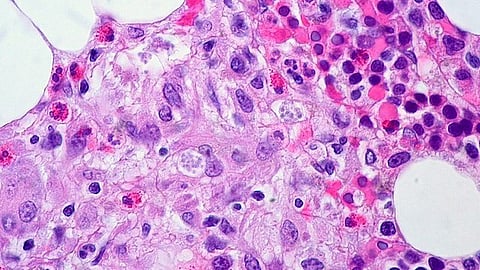

This new form of ringworm spreads through sexual contact and causes skin rashes that can appear on the face, limbs, groin, and feet. Unlike typical ringworm, which forms neat circles, TMVII rashes might look like eczema, leading to delayed treatment.